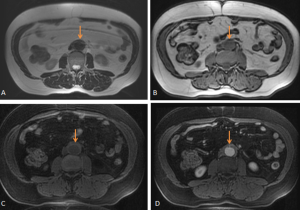

MAGNETIC RESONANCE IMAGING (MRI)

MRI offers superior soft-tissue contrast and enables non-contrast visualisation of the renal collecting system, making it particularly valuable in patients with renal impairment.

RPF is typically hypointense on T1-weighted images with variable intensity on T2-weighted images as well as in apparent diffusion coefficient values depending on the degree of active inflammation [2,3].